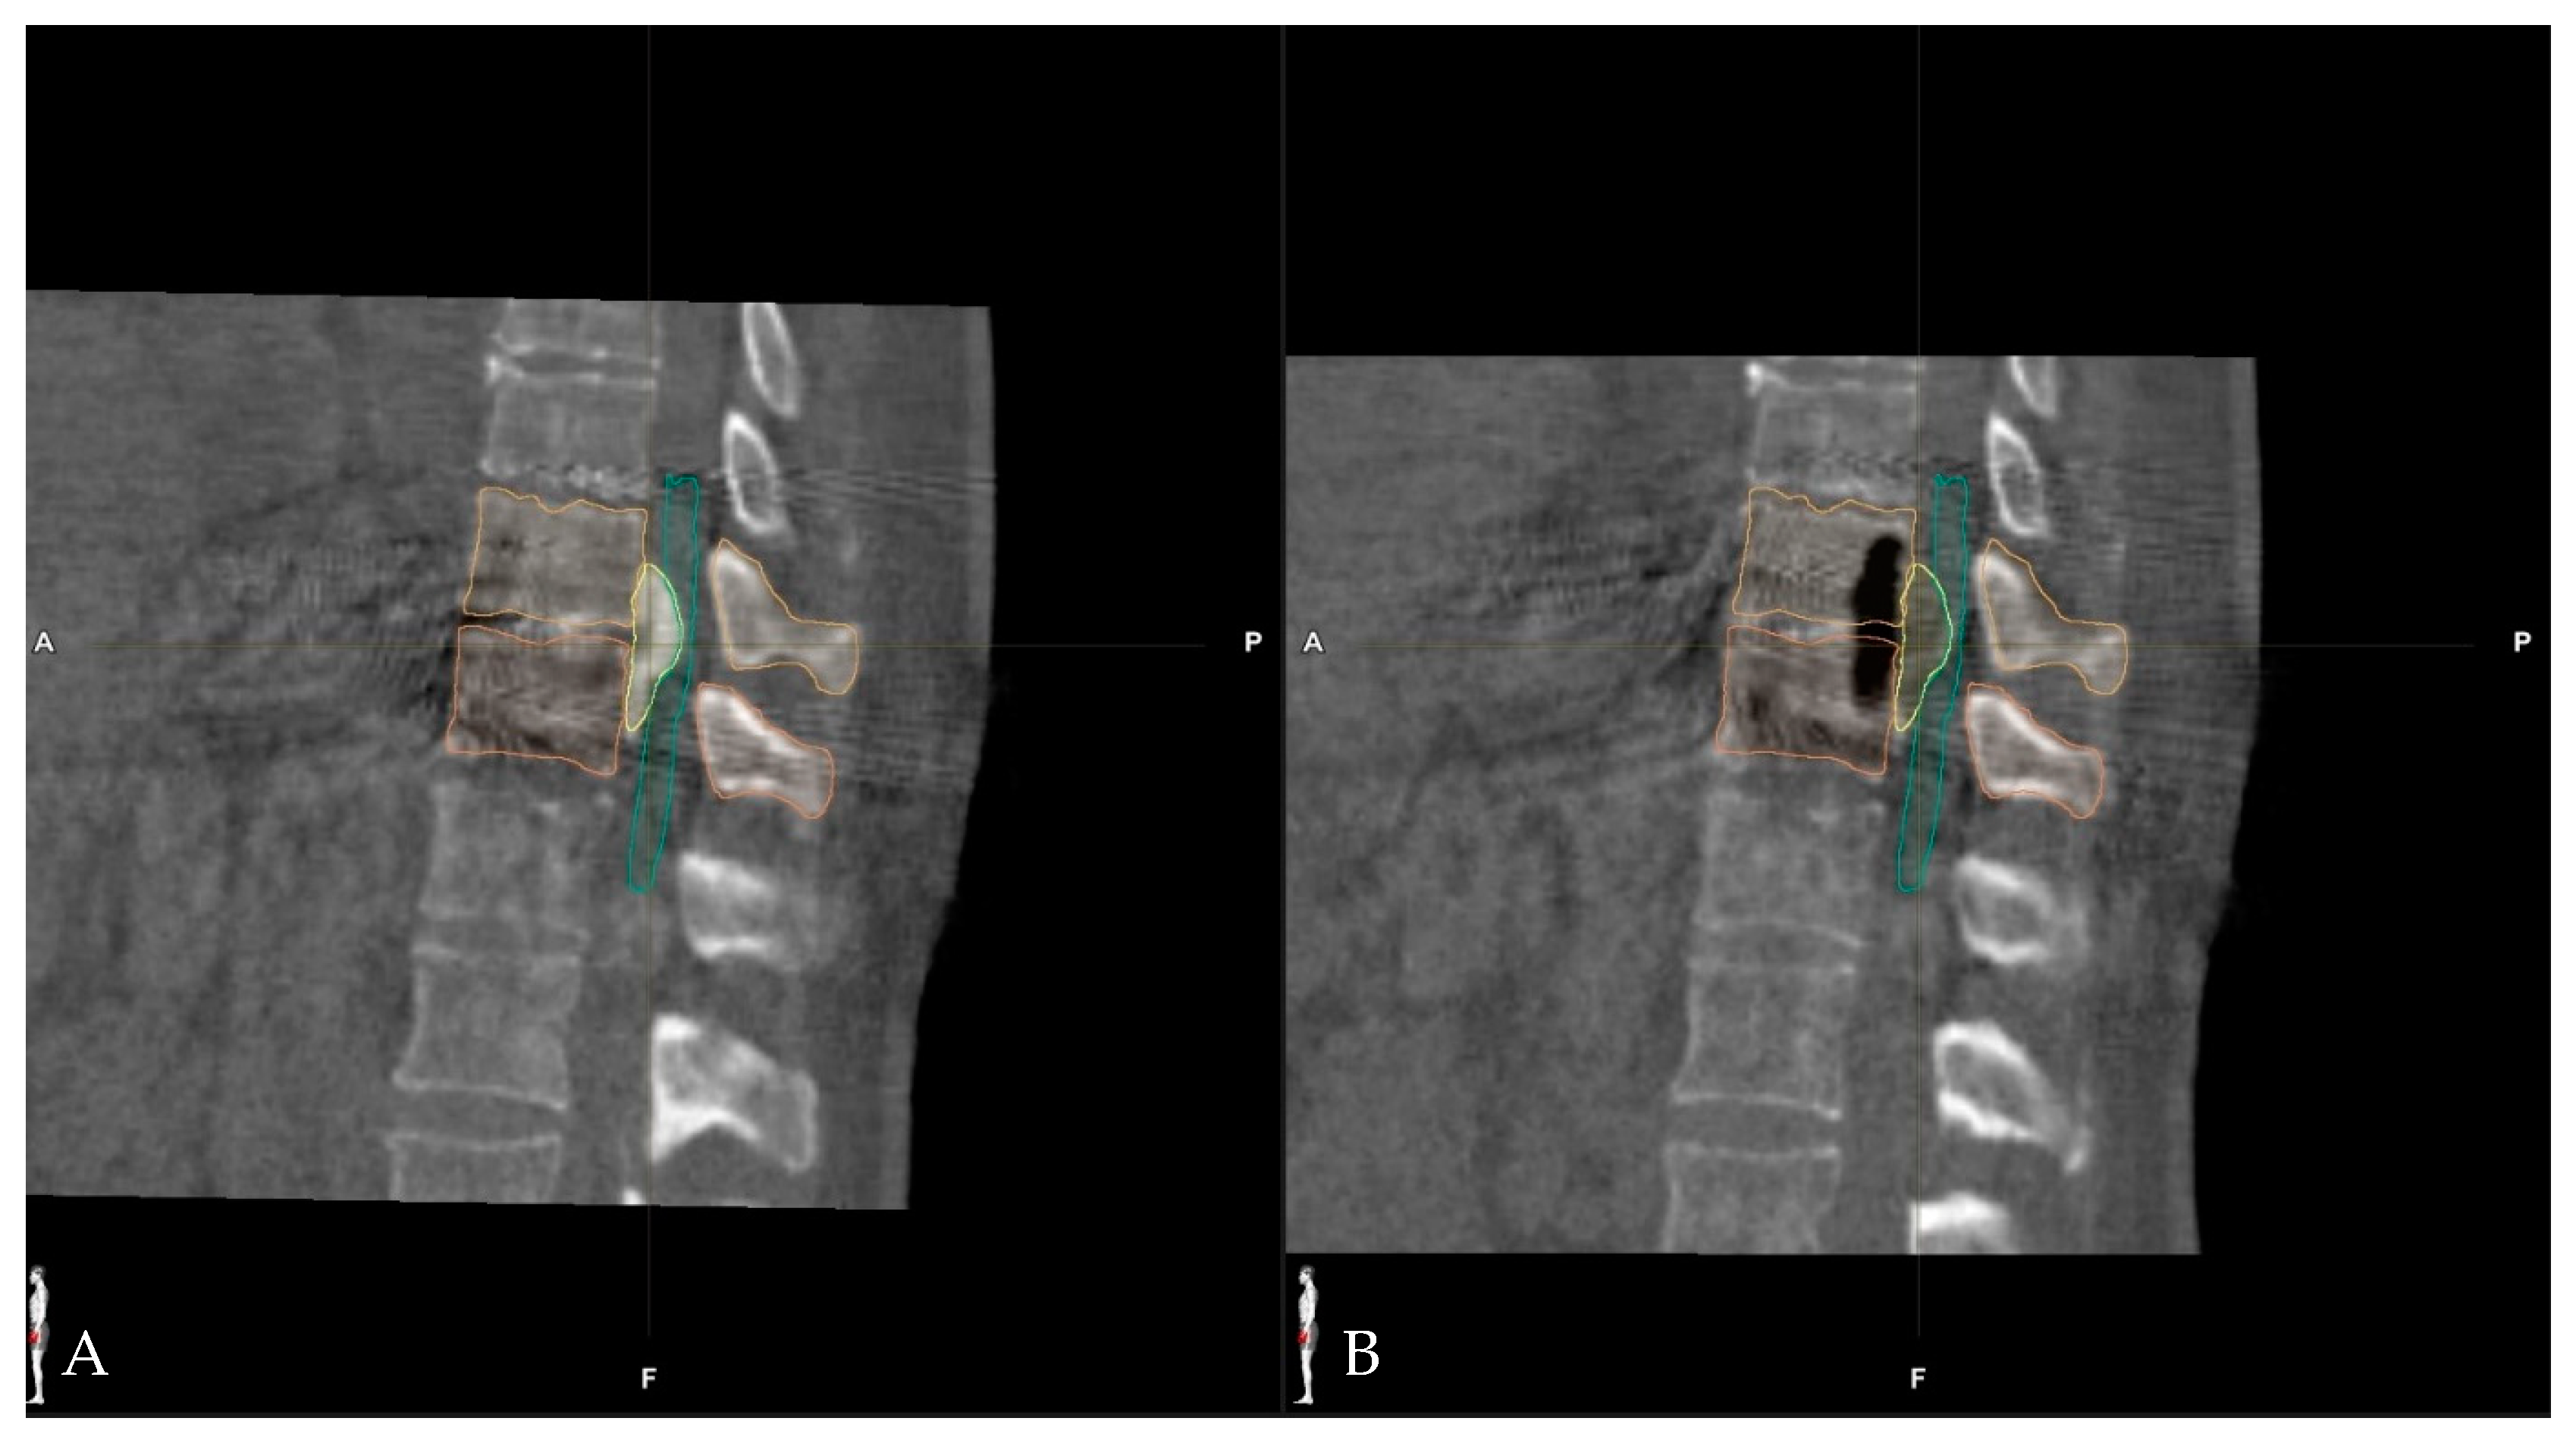

Surgical Treatment of Calcified Thoracic Herniated Disc Disease via the Transthoracic Approach with the Use of Intraoperative Computed Tomography (iCT) and Microscope-Based Augmented Reality (AR)

5.3. Use of Navigation and Intraoperative Imaging in the Resection of Herniated Thoracic Discs